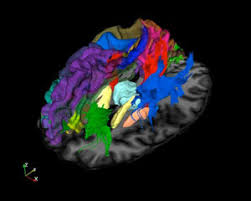

Since the first X-ray images were produced at the end of the 19th century, medical imaging has provided information of vital importance about the inner structure and function of the body for clinicians and scientists. Biomedical imaging techniques have developed in recent years into a compendium of increasingly powerful technologies that are used not only for diagnosing diseases but also for the study of biological structure and function, of metabolism and physiology, and of fundamental molecular and cellular processes. The development in the past two decades of new and more powerful imaging technologies such as MRI and PET, coupled with the explosive growth in the power of digital computers, have dramatically changed the nature of biomedical imaging science. Imaging plays a central role in patient management and care and provides crucial insights into the pathophysiology of many types of disease, such as cancer and neurological disorders. In addition, in vivo imaging methods also have widespread application in the elucidation of biological structure, in the study of basic biological functions and physiological processes, and in drug discovery. For example, the development of functional brain MRI (FMRI), and the study of brain neurochemistry by MR spectroscopy and PET imaging, are recent advances that promise to have a major impact on our understanding of how the brain works. New technological developments and advances in molecular sciences have expanded the applications of imaging to many new areas of medicine, such as the study of the effects of genetic modifications and of gene expression in animals.

| VUIIS operates state-of-the-art facilities for imaging research at all scales including imaging animals and human subjects. We pursue research in developing new imaging methods as well as applications in cancer, neuroscience, metabolic disorders, cardiovascular disease and other areas. VUIIS is supported by grants from the NIH, NSF, DOD, DOE, industry and foundations, as well as Vanderbilt University. |